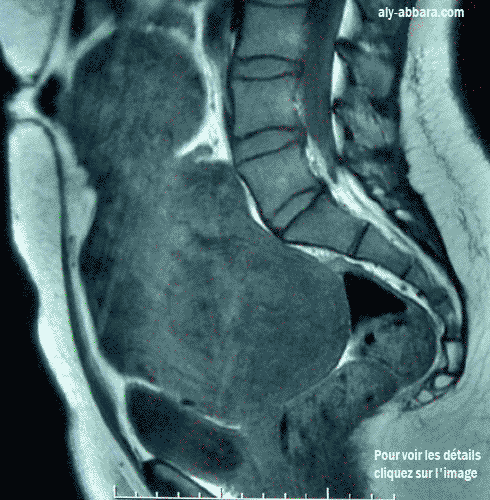

Utérus polymyomateux très volumineux

IRM (Imagerie par résonance magnétique)

Coupe sagittale médiane de la moitié inférieure de la cavité abdominale

Utérus polymyomateux occupant la totalité du petit pelvis et dépassant l'ombilic de quelques cm

(il a la taille d'un utérus gravide de 26 à 28 semaines d'aménorrhée)

Il est à l'origine de douleurs abdomino-pelviennes et de métrorragie